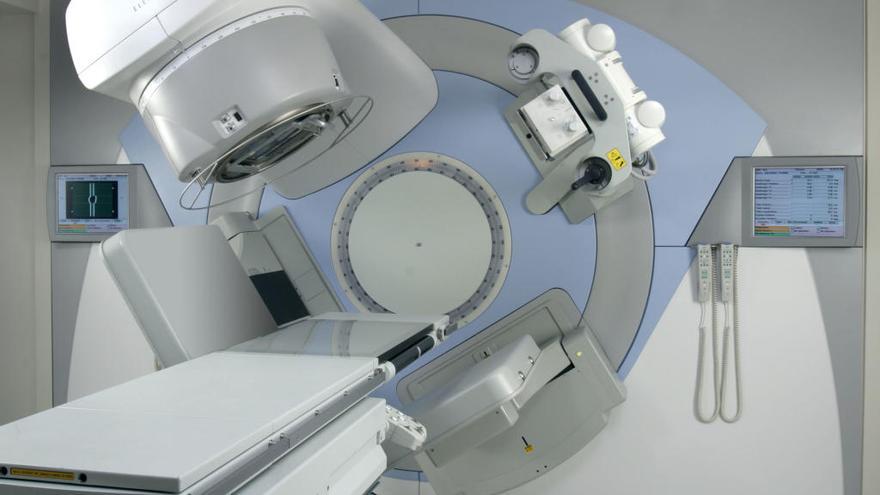

Los responsables de Sanidad en la Junta de Castilla y León han dado a conocer que el acelerador lineal donado por Amancio Ortega entrará en funcionamiento el próximo año 2018, una buena noticia y una mejora para la atención a pacientes con cáncer.

El primer acelerador se implantó en Zamora en 2004. Este aparato está destinado a procurar sesiones de radioterapia a los pacientes que lo precisan. La vida útil de aquel aparato se cifró en una década, con lo que el relevo era ya necesario. Entonces, estaba ya previsto el futuro cambio y se adaptaron las instalaciones en el búnker construido al efecto para que se pueda instalar el nuevo aparato sin que deje de funcionar el nuevo.